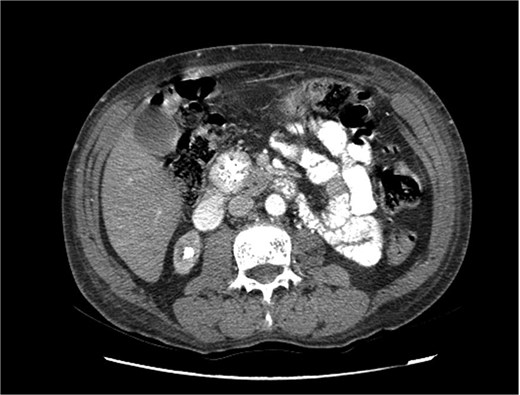

Upon admission in January 2025, the patient presented with altered mental status, dehydration, and hypoglycemia. The recurrence of hypoglycemic episodes was confirmed by laboratory studies and imaging, which identified a well-defined 3 cm mass in the pancreatic head on triphasic computed tomography (Figs 1–3). Given the diagnosis of recurrent malignant insulinoma and the possibility of resection, a surgical approach was chosen.

Triphasic computed tomography of the pancreas, portal phase, showing a tumor in the head of the pancreas.